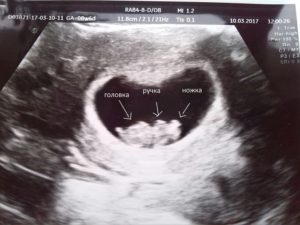

2. УЗИ.

Если при ультразвуковом исследовании диагностирована замершая беременность, видео «показывает» отсутствие сердцебиения у плода.

- Проведение УЗИ — диагностики, где на экране будет отсутствовать показатели сердцебиения плода.

Во время ультразвукового исследования врач может обнаружить замершую беременность. Этот метод считается «золотым» стандартом при диагностике данной патологии. Отсутствие сердцебиений и отставание плода в размерах – главные симптомы замершей беременности при УЗИ.